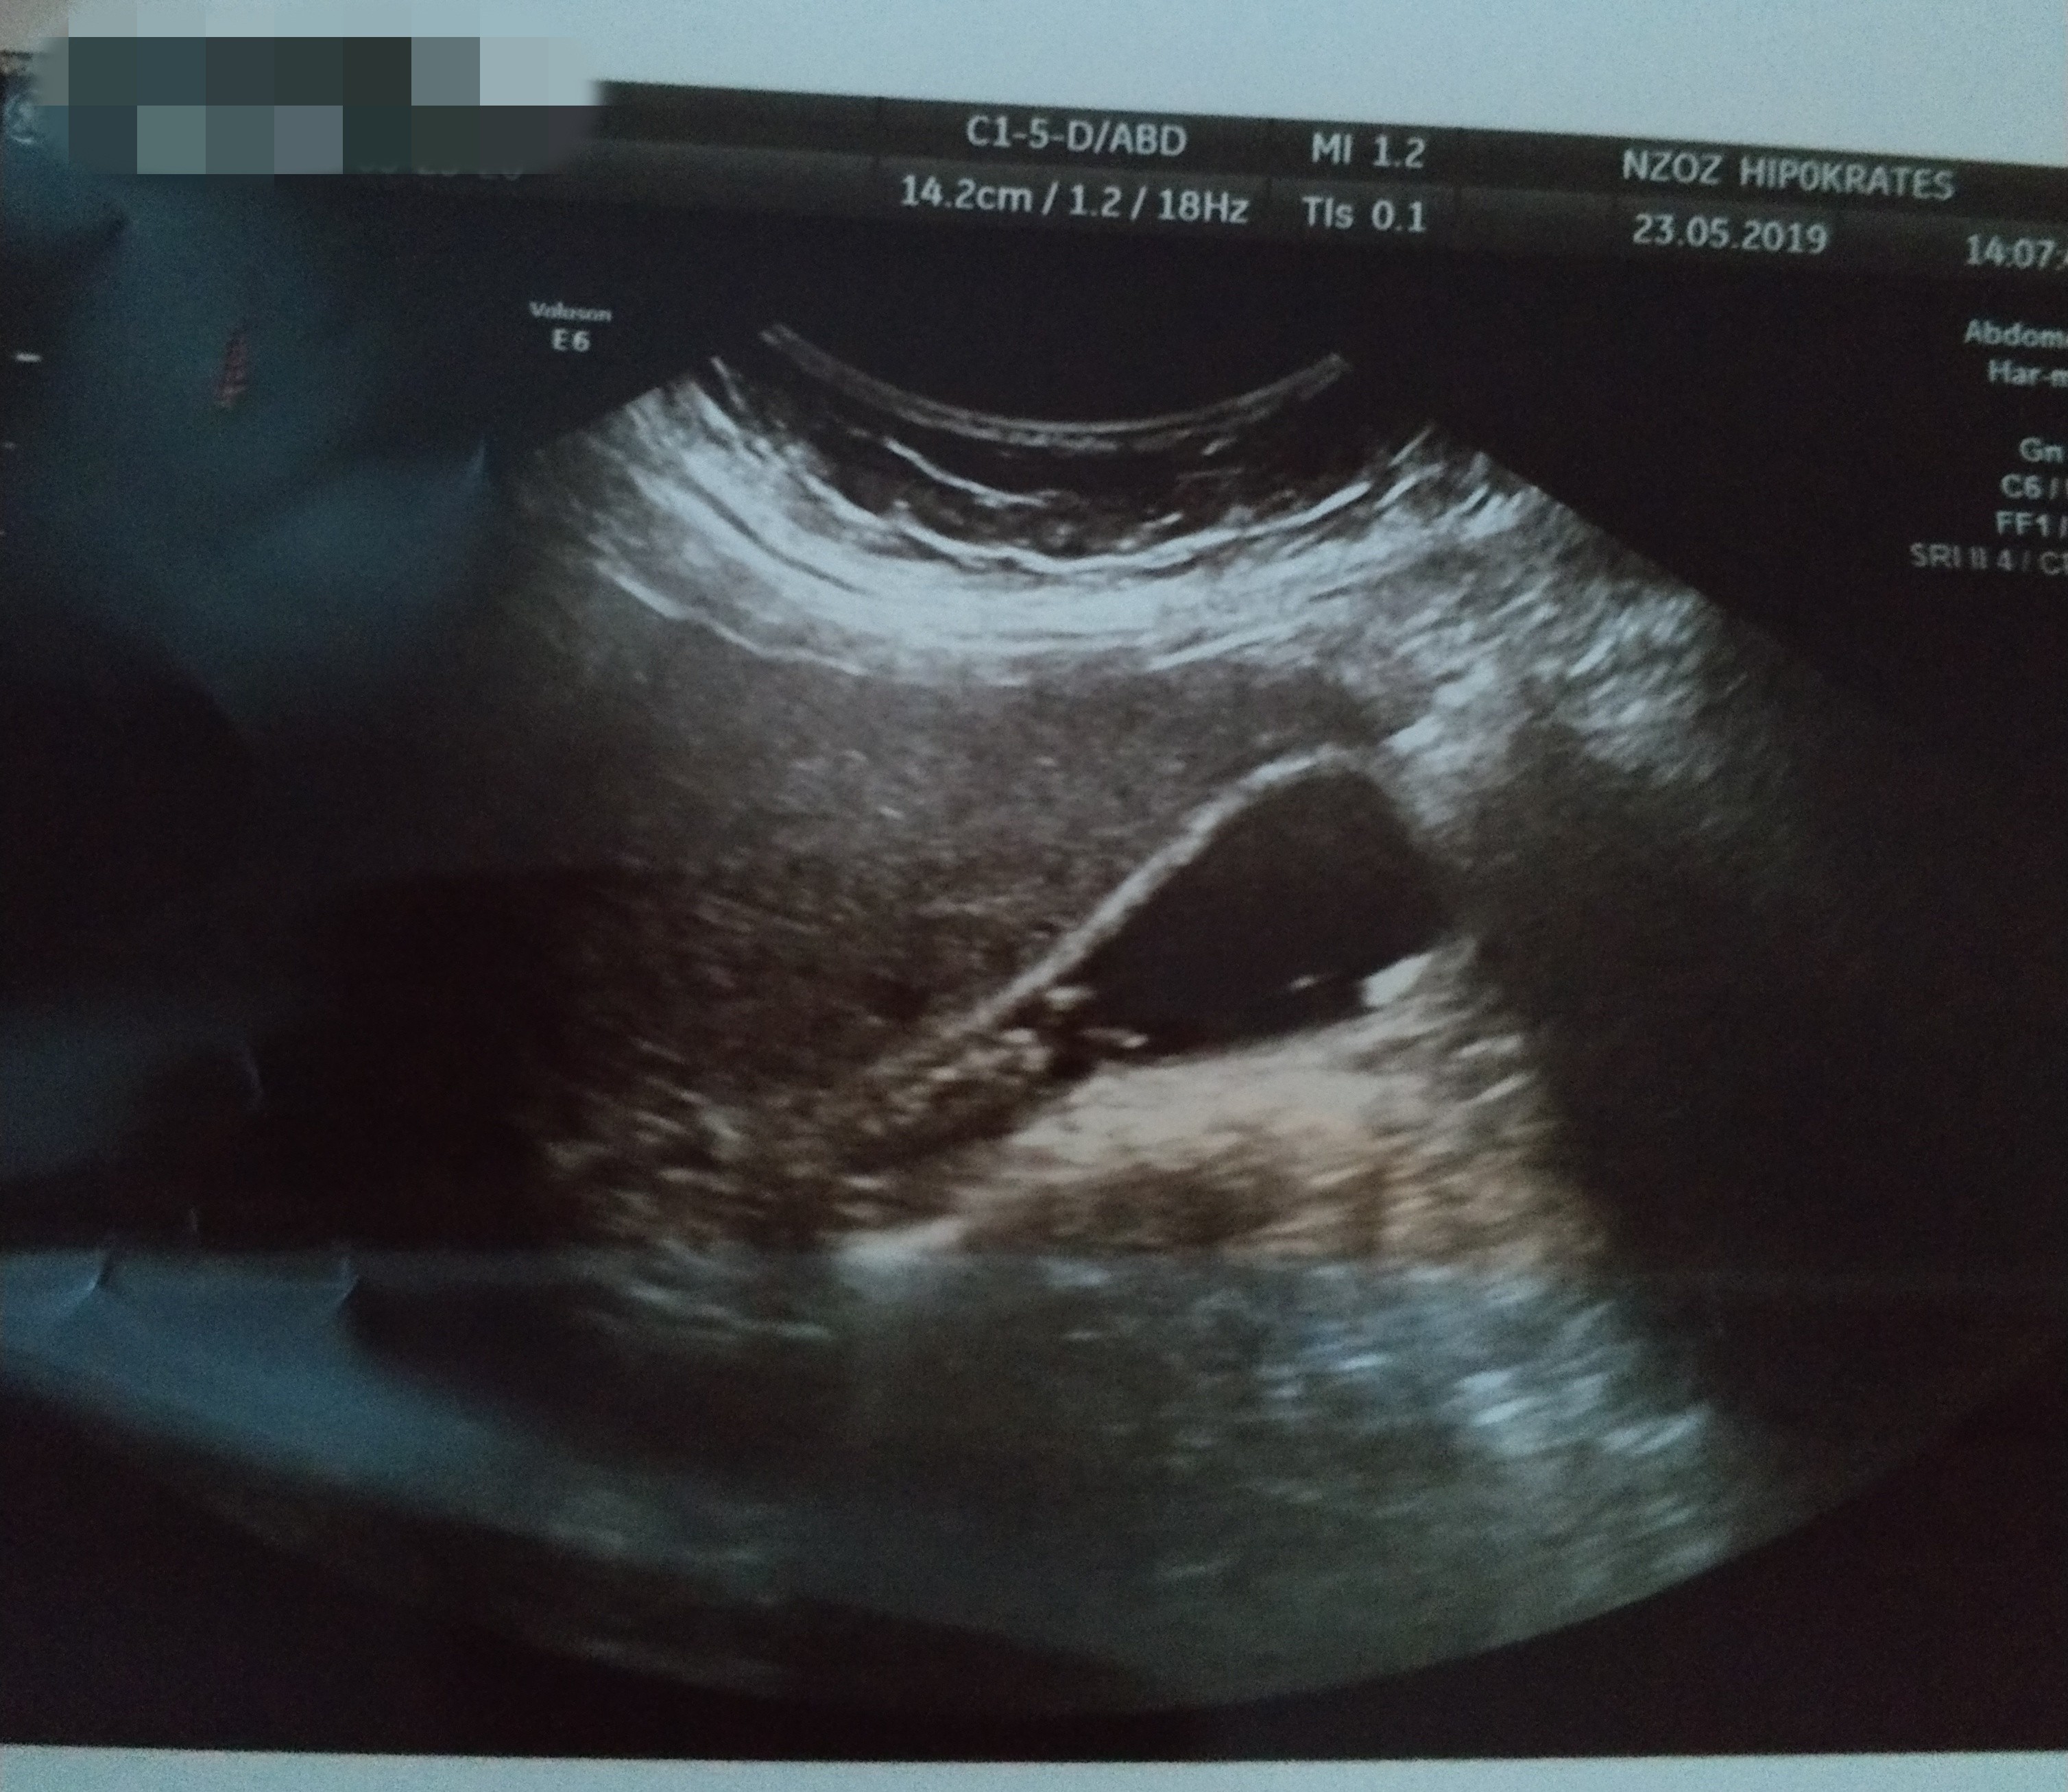

Jestem dzis po Usg brzucha. I juz nie musze isc na gastroskopie. Mam diagnoze. Bardzo liczne kamienie w woreczku zolciowym o wielkosci od 4 do 10mm.

Przedstawiam wam moich niechcianych lokatorów..

IMG_20190523_210824.jpg